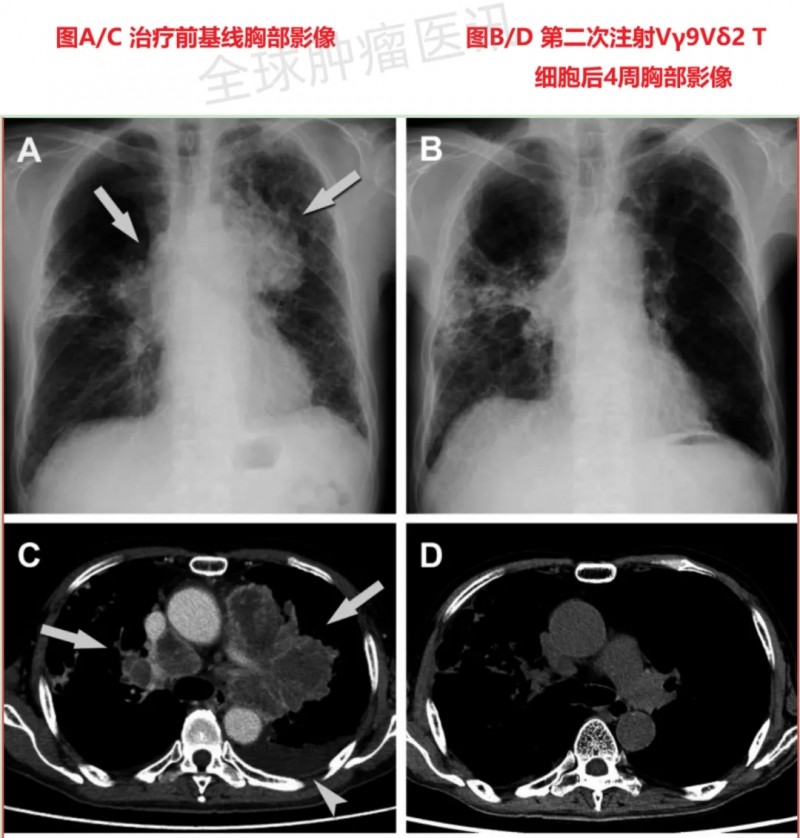

值得一提的是,其中1例66岁男性患者(编号TU-2844)的治疗效果尤为突出:该患者为左上叶原发性肺癌伴脑转移,病理诊断为大细胞神经内分泌癌,此前接受全脑照射、CDDP+VP-16全身化疗后病情仍持续进展,二线TS-1化疗也因腹泻被迫停止,最终入组接受Vγ9Vδ2T细胞治疗。接受治疗后,患者肺部肿瘤及肿大淋巴结显著缩小(详见下图);治疗期间虽短暂出现发热、咳嗽等症状,但经全身类固醇与抗生素治疗后迅速缓解。

▲图源“J Immunother Cancer”,版权归原作者所有,如无意中侵犯了知识产权,请联系我们删除